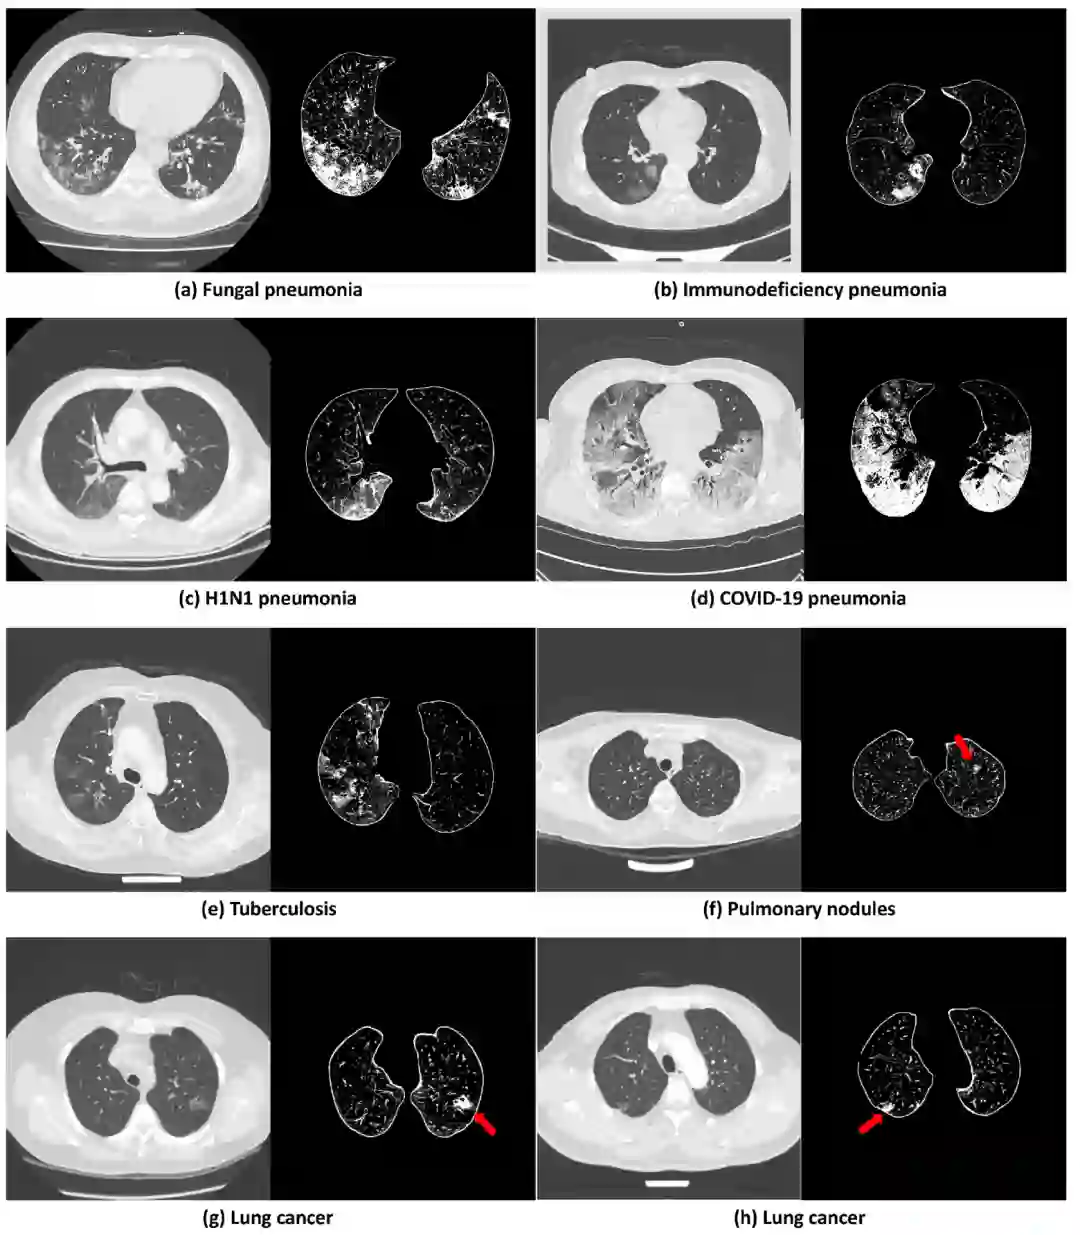

作者们通过其它实验说明了DLPE方法的潜力。第一,DLPE可以去除scan-level bias,因此可以提高量化的准确度和模型的精确性。第二,DLPE有着极强的泛化能力,甚至能用于有严重肺病的CT。第三,DLPE有助于帮助医学专家分析其它肺部疾病,如真菌性肺炎、免疫缺陷性肺炎、甲型流感肺炎、肺结核、肺小结节以及肺癌等()。

Extended Data Fig.2. DLPE在各种肺病上的表现:模型能很稳定地应用于各种肺部疾病。